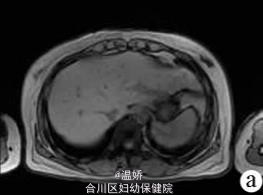

人肝片形吸虫病1例报告

患者,女,41岁,因肝区胀痛2个月余人院。2个月前无诱因出现肝区胀痛,伴发热(体温最高38℃),当地医院予抗感染后疼痛症状缓解,体温下降但此后症状时有反复发作。入院1d前当地医院腹部CT平扫提示肝左叶低密度灶。